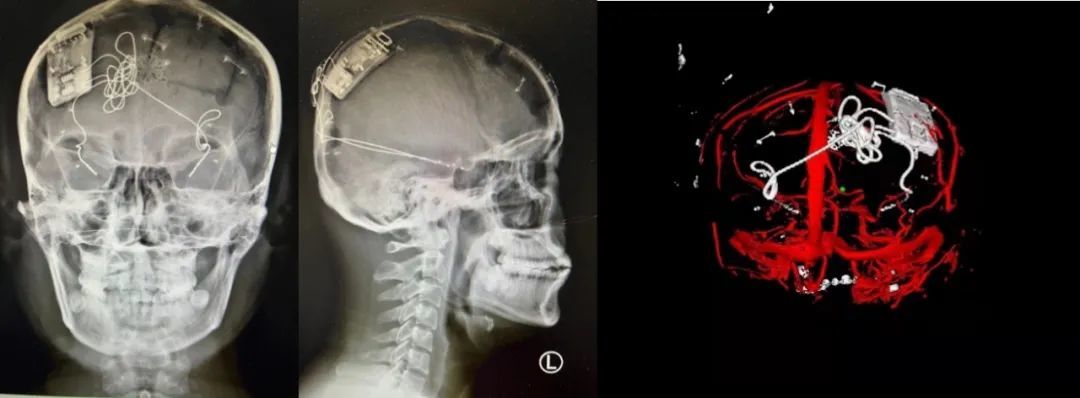

本次手術(shù)過程順利,術(shù)中刺激器各項(xiàng)指標(biāo)均工作正常,術(shù)后重建顯示電極位置精準(zhǔn),腦電信號(hào)清晰?;颊邽槟行?,入院后診斷為雙側(cè)顳葉癲癇,此類癲癇為開顱手術(shù)的相對(duì)禁忌癥,在藥物無法控制的情況下,傳統(tǒng)治療效果欠佳 。

術(shù)前經(jīng)過宣武醫(yī)院癲癇多學(xué)科專家團(tuán)隊(duì)詳細(xì)的臨床評(píng)估,包括視頻腦電監(jiān)測(cè)、頭顱磁共振及三維 CT 掃描、腦核醫(yī)學(xué)檢查等,全面評(píng)估了患者病情及致癇灶定位情況。

由于患者臨床診斷為雙側(cè)顳葉癲癇伴海馬硬化,無法通過致癇灶切除等傳統(tǒng)外科手術(shù)方式獲益,決定進(jìn)行閉環(huán)反應(yīng)性神經(jīng)刺激系統(tǒng)植入手術(shù)治療。并根據(jù)閉環(huán)神經(jīng)刺激技術(shù)特點(diǎn),為患者“量身定制”植入方案,尤其是電極植入位點(diǎn)和脈沖發(fā)生器固定部位等,為手術(shù)的順利實(shí)施奠定了良好基礎(chǔ)。

團(tuán)隊(duì)根據(jù)術(shù)前計(jì)劃,在手術(shù)機(jī)器人輔助下完成雙海馬長軸電極及 IPG 植入,術(shù)后重建顯示電極位置精準(zhǔn),腦電信號(hào)清晰。術(shù)后第二天,患者即下床活動(dòng),身體狀況恢復(fù)良好。